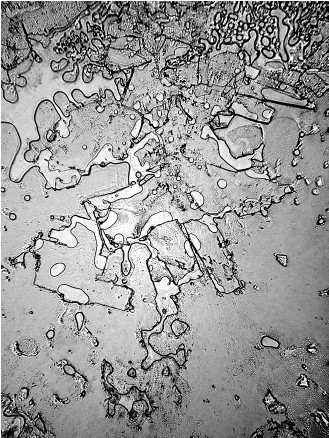

Dacă, pe aceste tipuri diferite de lacrimi, dar și pe altele, punem microscopul, la propriu, vom putea observa lucruri total surprinzătoare.

Cercetătorii Institutului de Oftalmologie din Madrid au analizat la microscop textura diferitelor lacrimi, iar rezultatul a fost unul neașteptat.

Compoziția lor poate părea asemănătoare sau chiar identică, uneori. Singura diferență constatată de noi, adesea, este gustul lacrimilor care pote fi, uneori, mai sărat, însă o imagine detaliată ne demonstrează că, în realitate, nu este deloc așa.

Fiecare categorie este diferită de cealaltă, iar compoziția lor diferă în funcție de sentimentele noastre.

Diferența o fac sentimentele exprimate prin intermediul lacrimilor, sunt de părere cercetătorii.

În funcție de situația în care se află sistemul neuroendocrin, în lacrimi se secretă diferite tipuri de hormoni și neurotransmițători, de a căror cantitate și tipologie depinde compoziția moleculară a lacrimilor înainte ca acestea să apară în exterior.